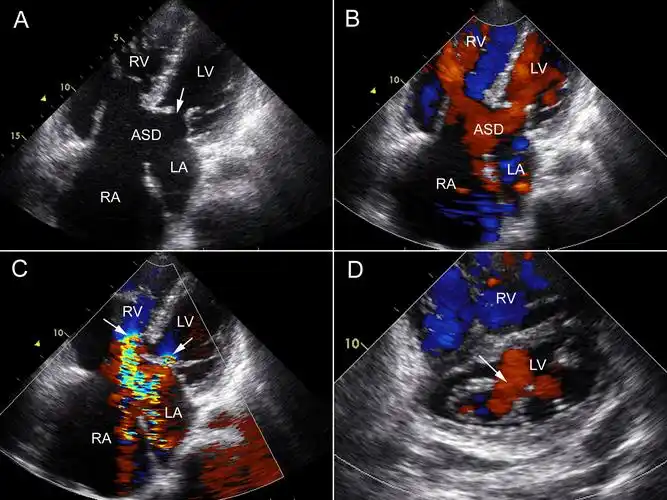

第7节 心内膜垫缺损 | 超声掌中宝